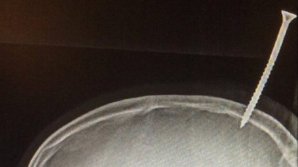

Taguri: şurub ÎNFRICOȘĂTOR! Un șurub de 15 centimetri a perforat creierul unui băiat de 13 ani MOMENT EXPLOZIV! Un bolid rămâne fără o roată chiar la start (VIDEO) 1 ABCDEFGHIJKLMNOPQRSTUVWXYZ IMPORTANTE ALTELE